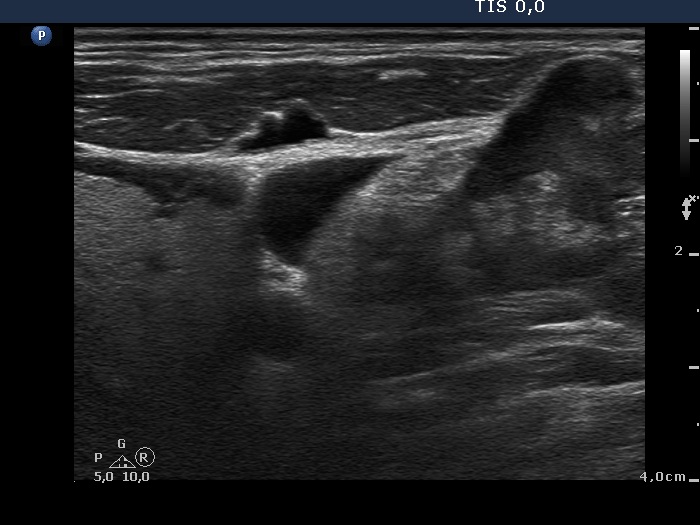

Lymph nodes in the neck - Case 2. (ultrasonographic picture 8)

Metastasis of an anaplastic adenocarcinoma of the lung

Left lobe and left supraclavicular region, horizontal scan. The intact left thyroid (left in the image) and a metastatic lymph node in the supraclavicular region (right in the image) in a common field of vision.